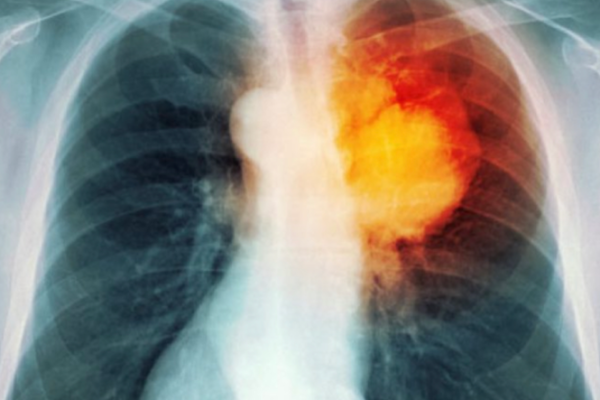

Pa mushkëritë nuk ka jetë. Ato janë të nevojshme për pastrimin e oksigjenit nga toksinat dhe transportimin e tij nëpërmjet gja kut drejt të gjithë…